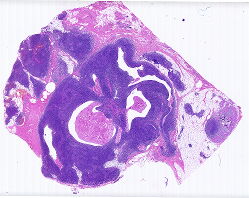

胸腺 |

女, 36岁, 近4个月来间断发热,就诊于当地医院,胸部CT示前纵隔血管前间... |

上海市第一人民医院 |

有诊断 |